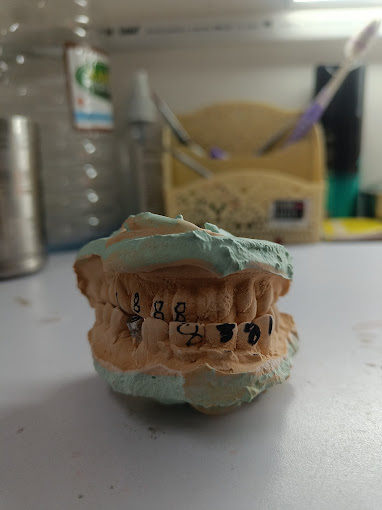

Ceramic crown with die cutting

Ceramic crowns with die cutting refers to a specific dental crown fabrication process where a detailed and precise model, known as a "die," of the prepared tooth is created and used to shape the ceram...